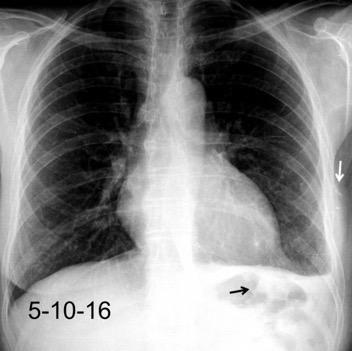

25. DERRAME PLEURAL. TRAUMA

26. DERRAME PLEURAL UNILATERAL. ENF. SUBDIAFRAGMÁTICA

27. DERRAME PLEURAL IZQUIERDO. URINOMA

28.DERRAME PLEURAL IZQUIERDO. PANCREATITIS AGUDA

29. DERRAME PLEURAL IZQUIERDO. SÍND. DE AFECTACIÓN POSTCARDIACA

30. DERRAME IZQUIERDO. SÍNDROME DE BOERHAAVE